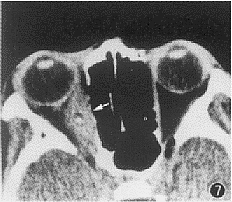

7 CT检查眶内囊尾蚴病 (活动期) , 右眼内直肌梭形增粗, 肌腹部有一圆形低密度区, 其内一斑点状高密度影 (箭头) , 为囊泡及头节影